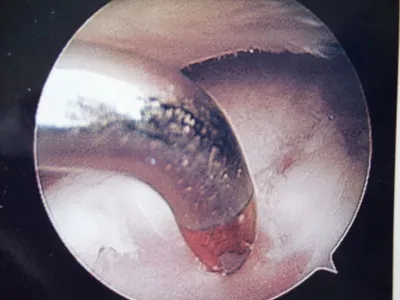

A series of intraop ankle arthroscopy pics of synovial chondromatosis with OCD talus and tibia and microfracture.

Pic of one of the nodules inside the ankle joint.